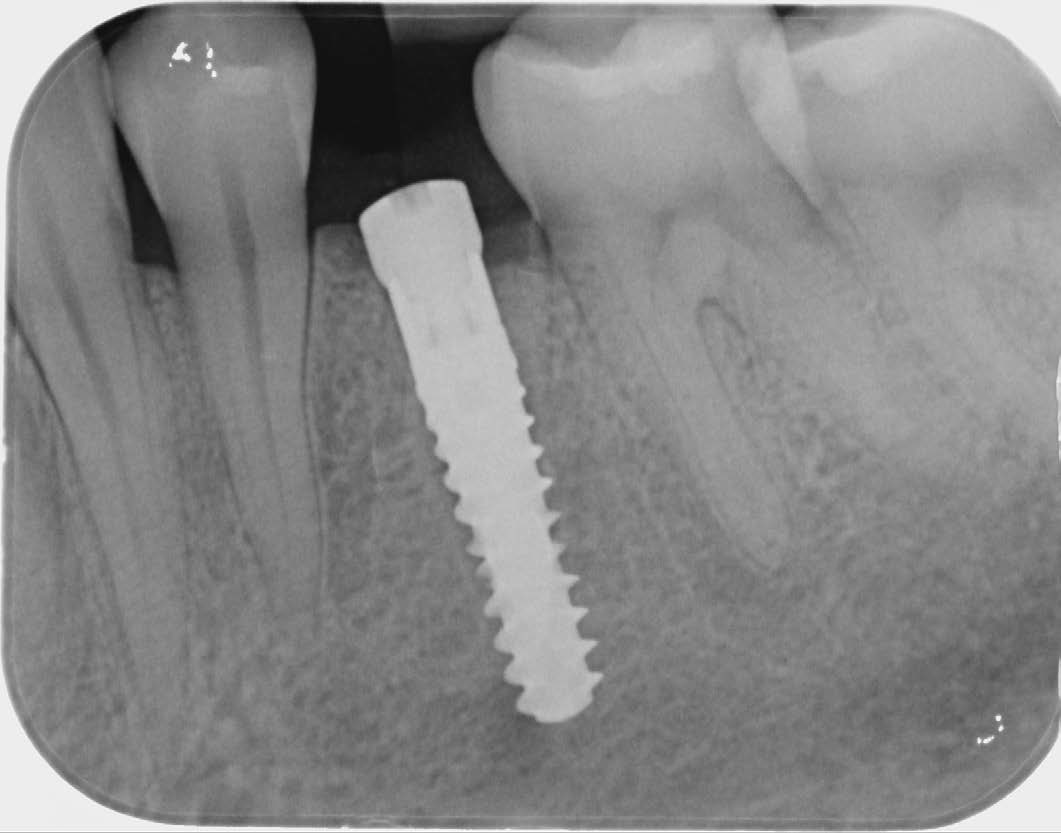

Fig. 6: Postoperative X-ray image of region 34, condition after immediate implantation. |

After osteotomy, I placed a 3.75 mm diameter implant, filled the gap between implant and root surface with allogenic bone substitute, inserted a provisional, and later restored with an aesthetic ceramic crown.